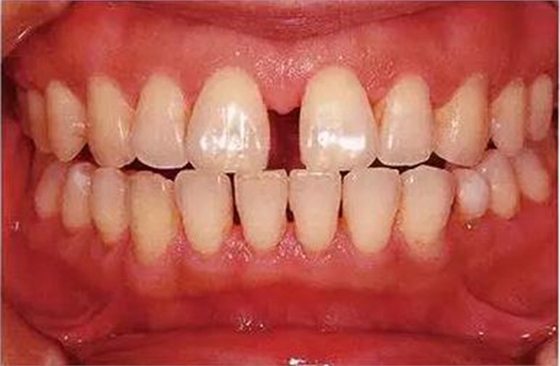

●參考病例② 25歲女性

25歲女性。菌斑控制狀態(tài)不好。齦溝除磨牙處外全在3mm以下,X光照片上左上、右下、左下的第一磨牙上有垂直性骨吸收。這個(gè)病例是參考病例①10年前的狀態(tài),是典型的侵襲性牙周炎局部型。